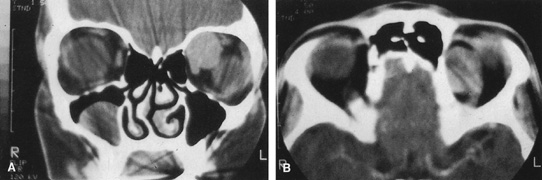

Fig. 11. A. Lateral canthotomy incision is made with straight iris scissors. B. Periosteum is elevated off of the lateral orbital rim. C. Wide undermining allows retraction of the skin incision to permit superior

and inferior osteotomies to be made with the air-driven saw. D. The bony rim has been outfractured. Because of the distensibility of the

skin, it is possible to remove a large bone flap through the small

canthotomy incision. E. The intraconal mass is extracted with the aid of the cryoprobe. F. The bone fragment is positioned for resuturing.

Fig. 11. A. Lateral canthotomy incision is made with straight iris scissors. B. Periosteum is elevated off of the lateral orbital rim. C. Wide undermining allows retraction of the skin incision to permit superior

and inferior osteotomies to be made with the air-driven saw. D. The bony rim has been outfractured. Because of the distensibility of the

skin, it is possible to remove a large bone flap through the small

canthotomy incision. E. The intraconal mass is extracted with the aid of the cryoprobe. F. The bone fragment is positioned for resuturing.

|